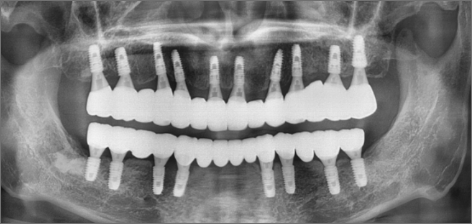

8년 후 : 2024.03.06치료 기간 : 2014.06.13 ~2024.03.06

8년 후 : 2024.03.06

치료 기간 : 2014.06.13 ~2024.03.06

THE 이해승치과에서 2014년에 치료 받으신 40대 환자분의 사례입니다. 흡연과 음주가 근본 원인이 되어 2014년 전악 임플란트 치료를 받으셨습니다. 감사하게도 저희와 함께 꾸준히 8년간 관리를 동행하시며 추가적인 전신 질환 없이 건강한 50대를 보내고 계십니다. 치료 경험을 통해 변화를 만드신 환자분을 존경합니다.